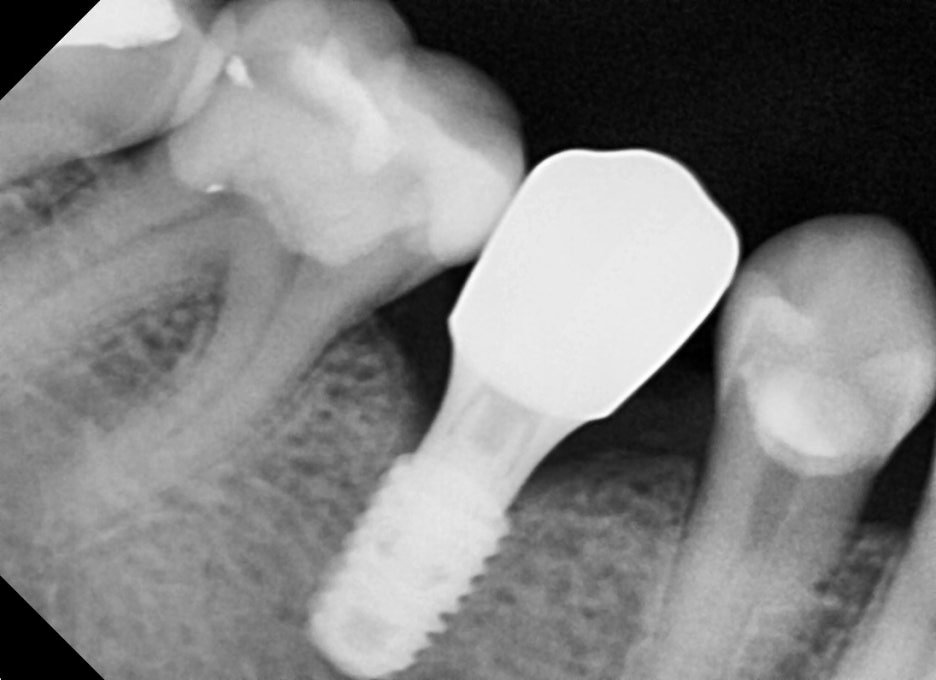

1.파노라마 촬영 결과, 오른쪽 아래 어금니는

치아가 파절되어 보존이 불가능했습니다.

발치 후 즉시 임플란트 식립이 가능한

상태로 진단되었습니다.

2.오른쪽 위 작은 어금니는 오래 전

상실된 치아였으나, 잇몸뼈의 흡수 정도가 심하지 않아

추가적인 뼈이식 없이 임플란트가 가능했습니다.

① 발치 및 임플란트 식립

– 깨진 치아를 발치한 뒤, 잇몸뼈 상태를 확인하고

바로 임플란트를 심었습니다.

② 임플란트 식립

– 결손 부위에도 동시에 임플란트를 진행했습니다. 뼈 상태가 좋아 추가 시술 없이 안정적으로

식립이 가능했습니다.